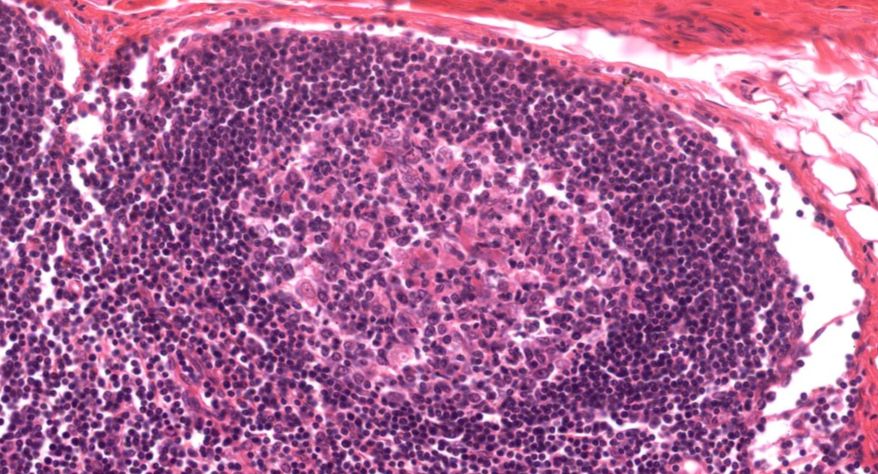

低倍镜:胸腺表面包有薄层结缔组织构成的被膜,结缔组织深入实质,将胸腺分成许多不完整的小叶。每个小叶分为周围的皮质和中央的髓质两部分。皮质中胸腺细胞排列密集,故染色深;髓质中胸腺细胞较少,胸腺上皮细胞多,故染色浅,其中可见染成红色的圆形小体-胸腺小体。高倍镜:胸腺小体大小不等,由几层至十几层扁平的胸腺上皮细胞呈同心圆状排列而成,其外周的细胞较幼稚,细胞核明显;小体中央部分的上皮细胞已退化,细胞核消失,胞质呈均质状,染成红色。

7.胸腺小体1

8.胸腺小体2